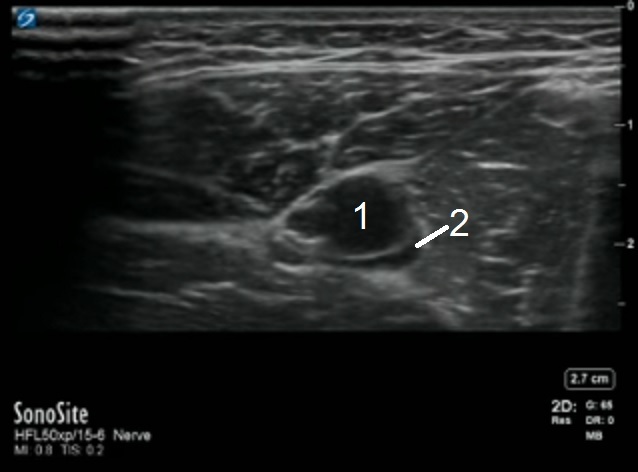

Adductor Femoral Vein Image

Femoral Artery

Femoral Vein